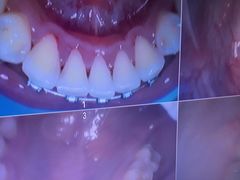

• 牙博士口腔品牌连锁(杨浦店)

• -牙博士口腔品牌连锁(杨浦店)